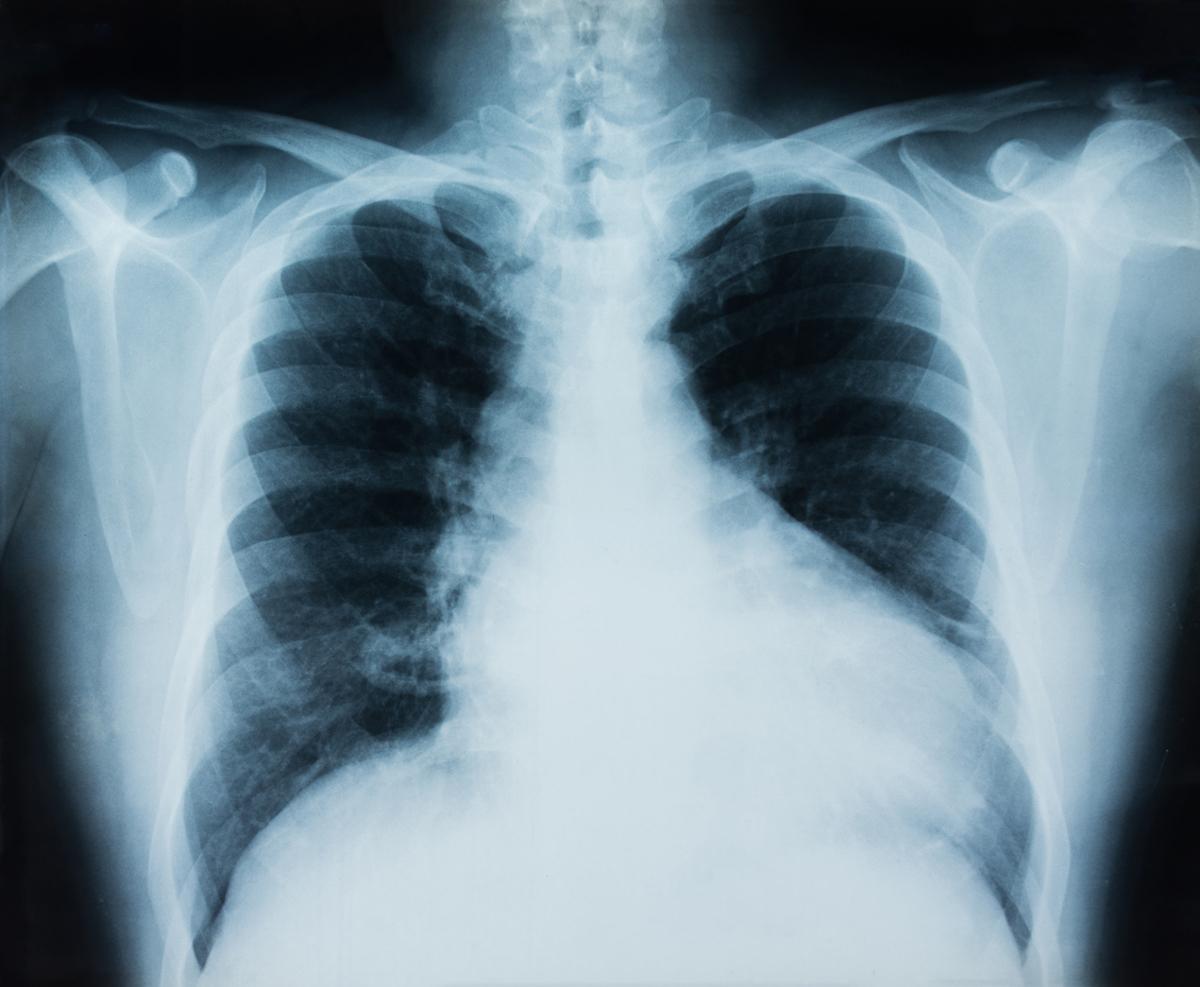

L’étude a porté sur 28 adultes atteints d'un cancer du poumon non à petites cellules (CPNPC) avancé. Des échantillons de sang ont été prélevés avant les traitements, puis à intervalles réguliers par la suite.